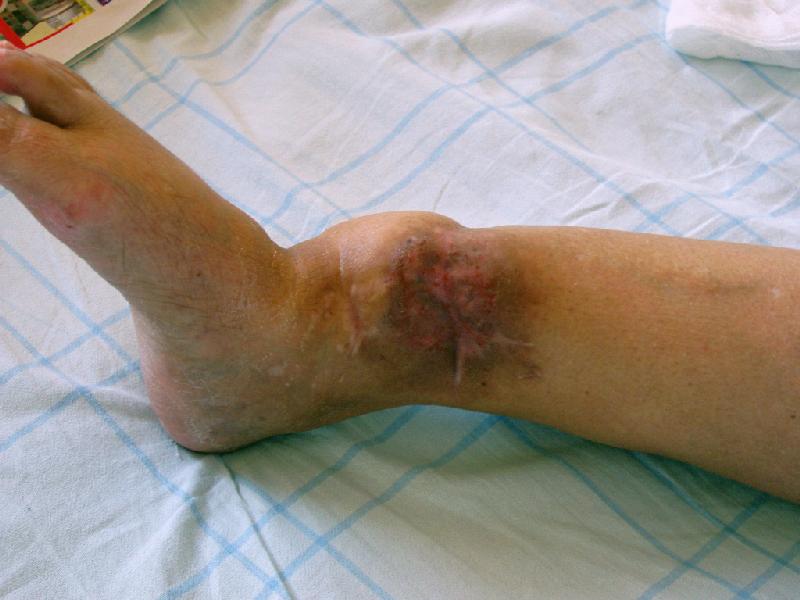

Глубокоуважаемые коллеги,Поступила женщина 72 лет. Полтора года назад - укушенная рана, перелом голени. Лечили аппаратом, не срослось. Долго не заживала рана.

Но вроде уже с полгода мягкие ткани закрыты. Спереди подпаянные рубцы. Есть приличная подвижность на уровне несращения. Картинки в приложении. Что предложите? Спсибо заранее.